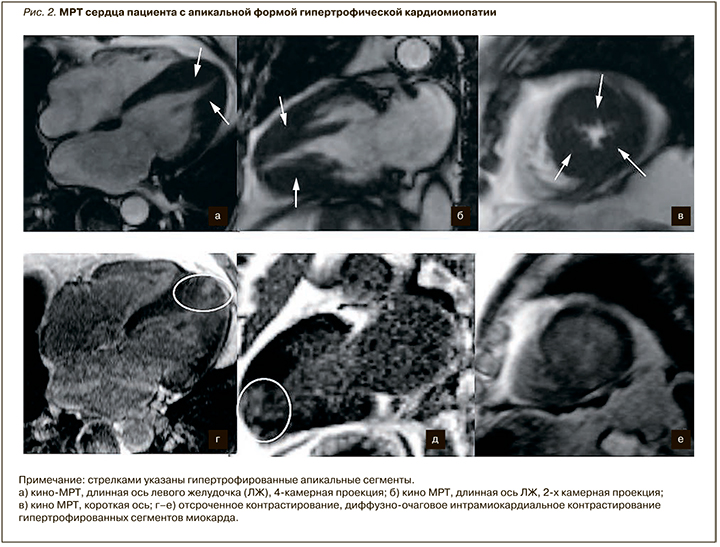

Морфологически выделяют несколько типов ГКМП. Наиболее часто встречается асимметричная гипертрофия ЛЖ, толщина миокарда (обычно МЖП) в конечно-диастолическую фазу при этом составляет более 15 мм. У некоторых пациентов гипертрофия миокарда может достигать крайне высоких цифр – до 45–50 мм. Кроме того, выделяют апикальную (рис. 2) и симметричную формы ГКМП. У 70% пациентов чаще всего в патологический процесс вовлекаются МЖП и передняя стенка ЛЖ. Наиболее выраженные изменения отмечаются, как правило, в базальных сегментах МЖП (предыдущее название этой формы – идиопатический гипертрофический субаортальный стеноз), при этом гипертрофия средних и верхушечных сегментов менее характерна. В некоторых случаях может наблюдаться вовлечение в процесс папиллярных мышц, а также миокарда правого желудочка. По сравнению с эхокардиографией (ЭхоКГ) у метода МРТ выше диагностическая точность в определении апикальной формы ГКМП, гипертрофии переднебоковой стенки, верхушечных аневризм и тромбов ЛЖ; также методика более чувствительна в определении малых аномалий у пациентов с саркомерными мутациями, таких как расщелины клефты (расщелины) миокарда и вариант строения папиллярных мышц [10–12].